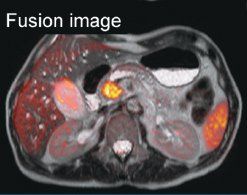

Figure 2 - Adenocarcinoma of head of pancreas. Comparative T2-weighted and diffusion-weighted imaging including fusion imaging and ADC map. Images courtesy of Dr. Matos.

In pancreatic imaging, DWI is more sensitive for detection of pancreatic lesions than conventional MRI (see Figure 2). If DWI reveals no unusual pathology, it can be confidently stated that the examination is normal, but with conventional imaging this is not always the case, according to Celso Matos, MD, an associate professor and head of the MRI division at Erasme Hospital at the Free University of Brussels.

However, in positive examinations, it can be difficult to differentiate the pathology visualized in DWI from cancer or pancreatitis. To increase specificity, DWI of the pancreas should always be part of a comprehensive study that includes conventional T2-weighted, MR cholangiopancreatography, and contrast-enhanced T1-weighted sequences, Dr. Matos said. He underlined the need for more validation. "We don't know if we are measuring cancer cell death through fibrosis or necrosis. We need to validate DWI techniques by comparing results with histopathology," Dr. Matos said.